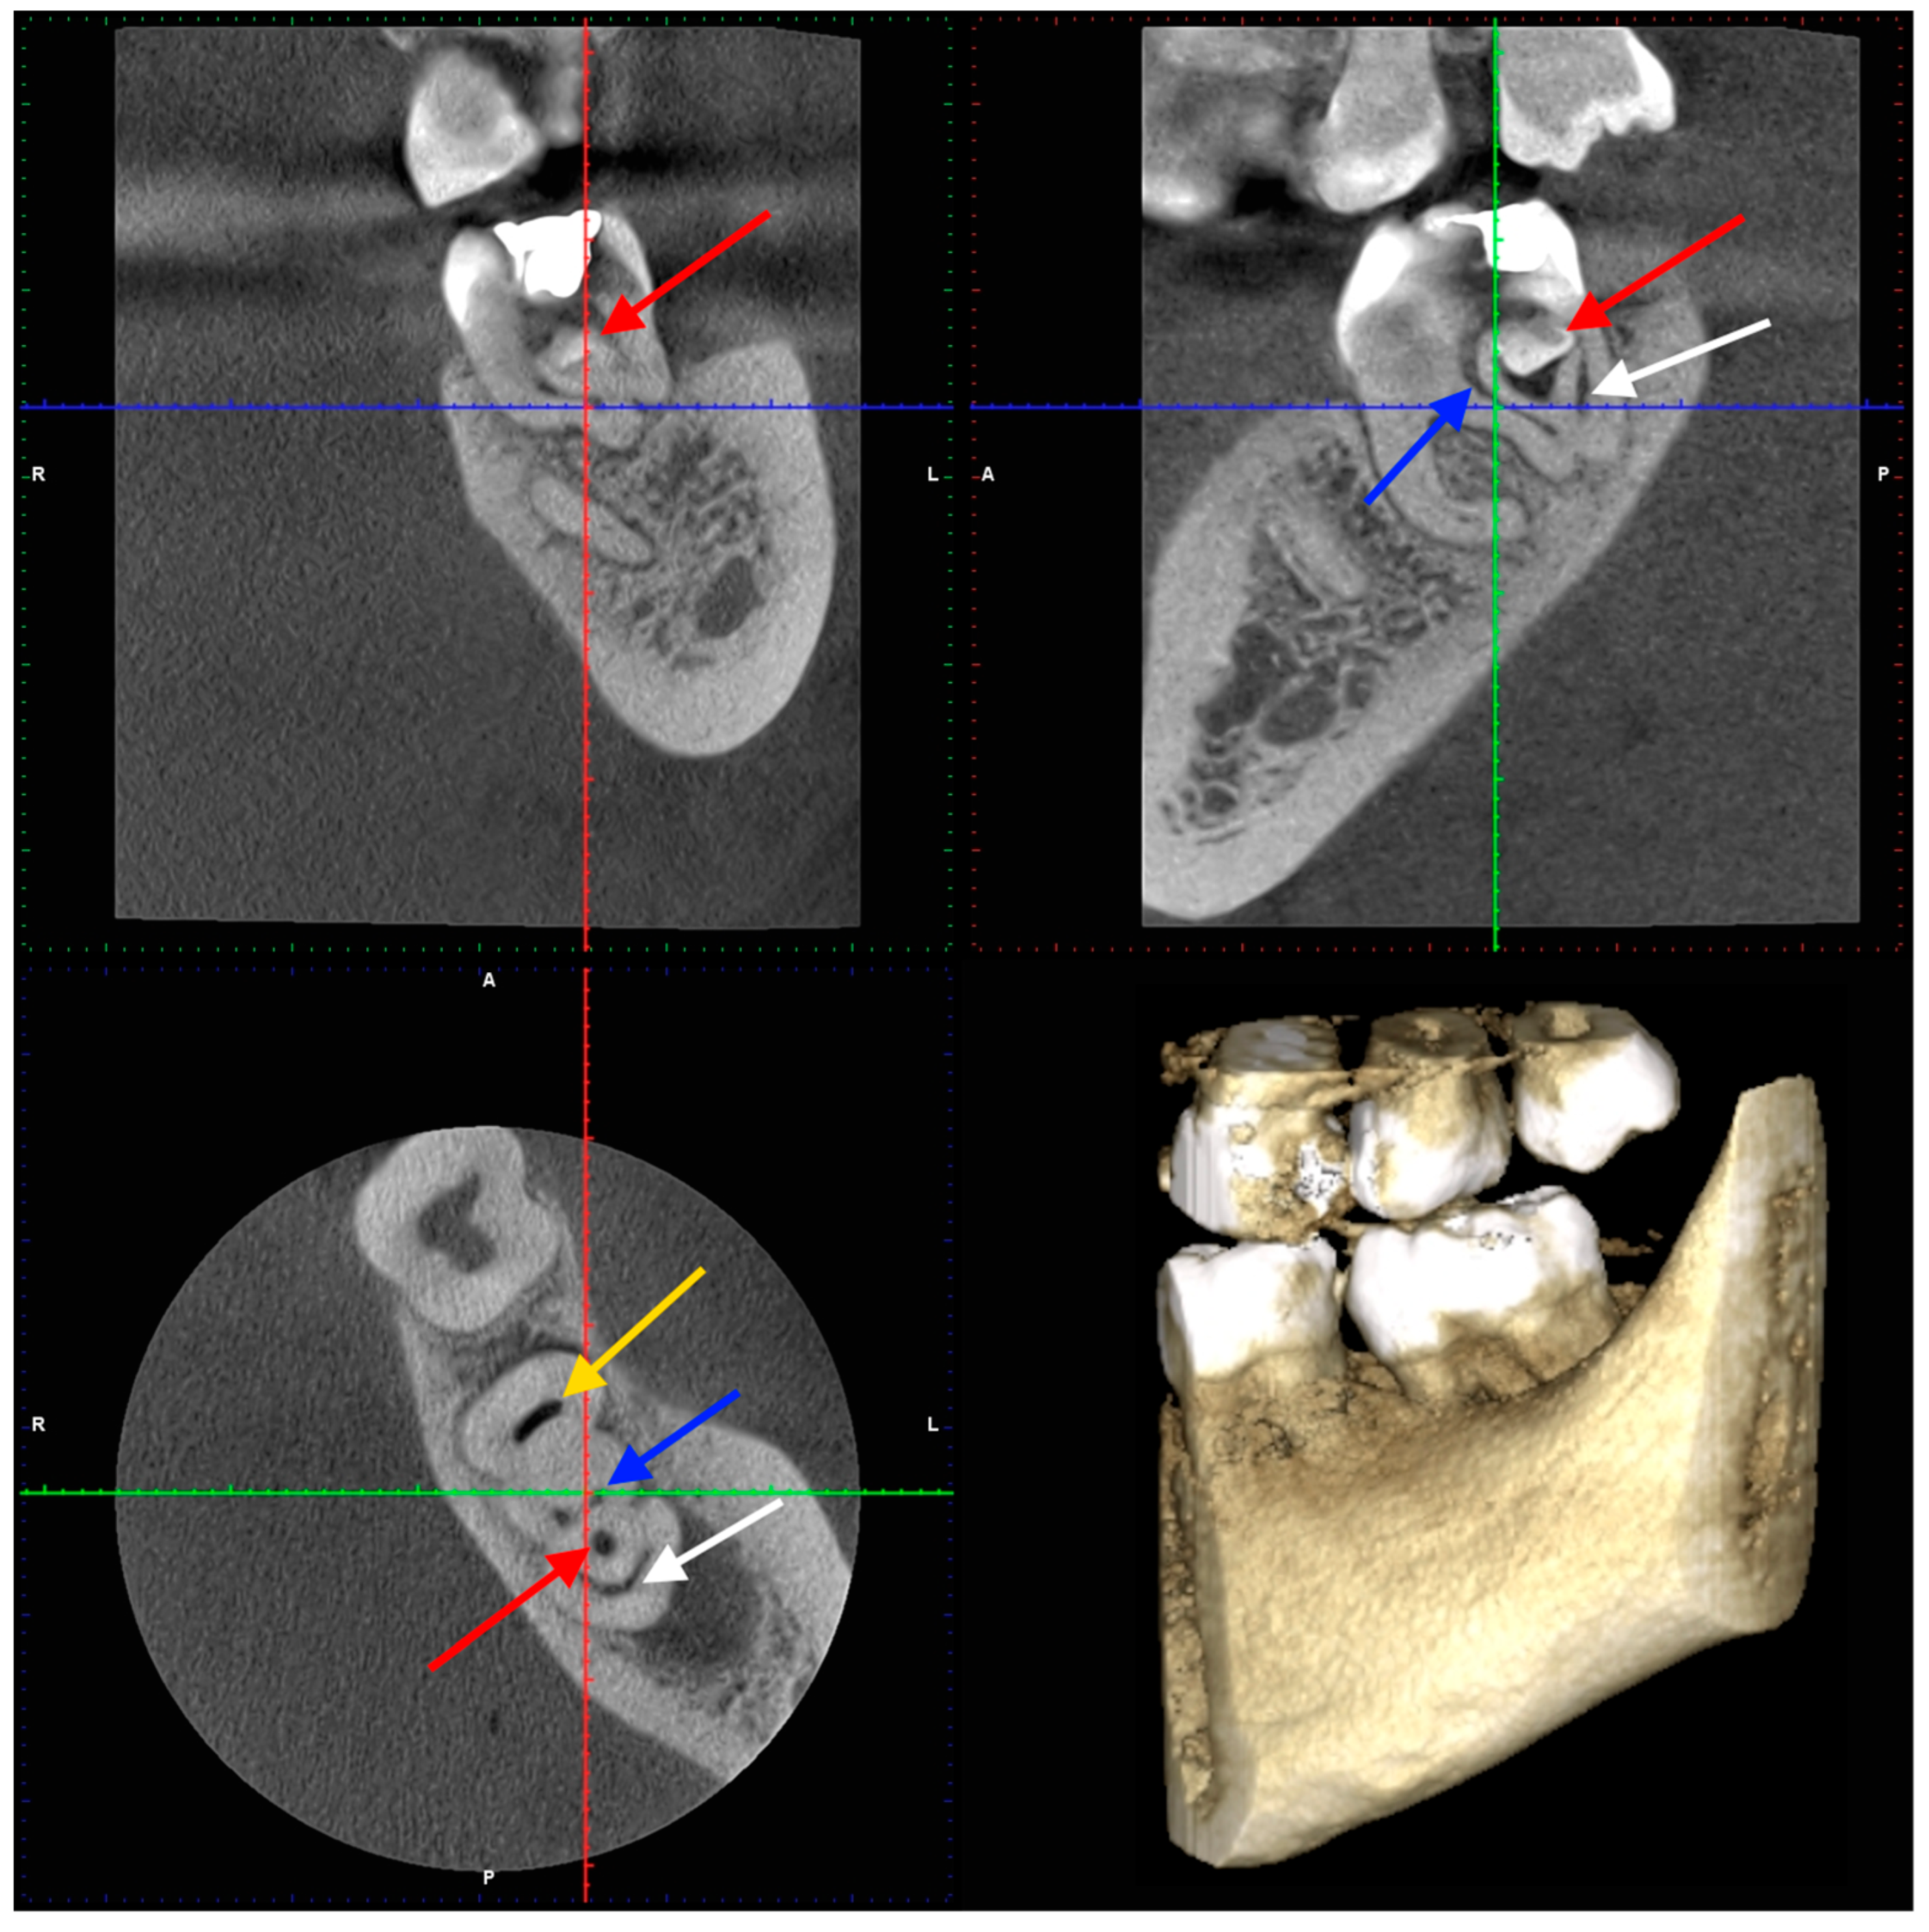

2. Case Presentation

2.1. The First Visit

2.2. The Second Appointment